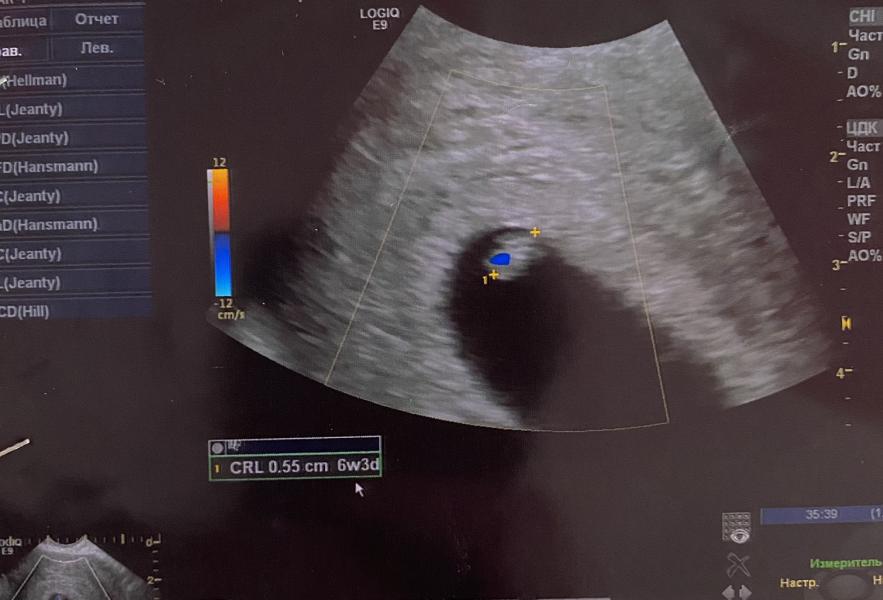

Сходила на узи☺️ даже послушала сердечко ♥️ соответствуем своему сроку

Ктр 5,5 мм

Жм 2,5 мм

ПЯ 31 мм